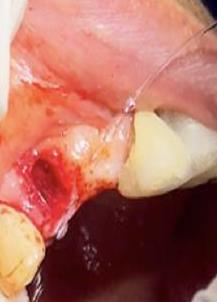

Sindesmotomía con un periostótomo de molt # 9, posteriormente se realizó la luxación con un elevador recto, buscando el punto de apoyo, seguido se efectuó la prensión con el fórceps 150 en el diente con sumo cuidado de no tocar la encía colocándolo hasta el cuello dental, haciendo movimientos de lateralidad y rotación hasta lograr la dilatación del alveolo, y finalmente la tracción del órgano dentario, observando que la raíz este integra, y que estructuras alrededor estén conservadas, de la misma forma se revisó el alveolo en busca de la presencia de granulomas o espículas óseas, una vez ya revisado se procedió al curetaje, con una cucharilla de lucas, se introdujo y se dio paso al retiro del exudado purulento, se realizó irrigación del alveolo con solución fisiológica, una vez limpio se realizó una sutura simple con sutura nylon, seda # 3/0 en el medio del alveolo con la finalidad de aproximar rebordes, evitar su contaminación por el ingreso de comida, además generar una mejor cicatrización en una zona estética , finalmente se aplicó presión por medio de una gasa que mordió el paciente por un lapso de 30 minutos, para contribuir con una hemostasia adecuada.

Figura 6. Sindesmotomía, luxación y prensión del incisivo lateral superior derecho pieza N.º 1.2

Elaboración: Los autores.